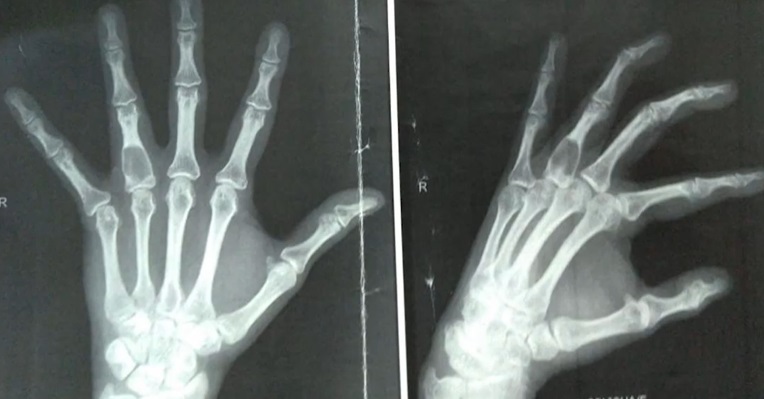

9

Q

Qual diagnóstico?

A

Encondromatose múltipla

Dx: Doença de Ollier

How well did you know this?